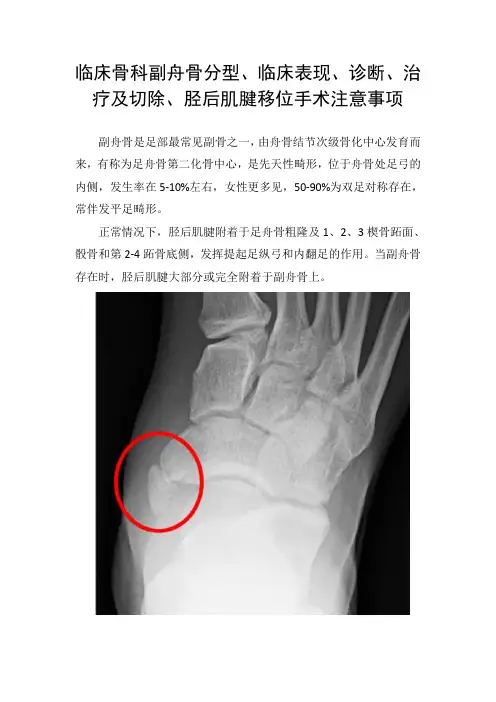

临床骨科副舟骨分型、临床表现、诊断、治疗及切除、胫后肌腱移位手术注意事项副舟骨是足部最常见副骨之一,由舟骨结节次级骨化中心发育而来,有称为足舟骨第二化骨中心,是先天性畸形,位于舟骨处足弓的内侧,发生率在5-10%左右,女性更多见,50-90%为双足对称存在,常伴发平足畸形。

正常情况下,胫后肌腱附着于足舟骨粗隆及1、2、3楔骨跖面、骰骨和第2-4跖骨底侧,发挥提起足纵弓和内翻足的作用。

当副舟骨存在时,胫后肌腱大部分或完全附着于副舟骨上。